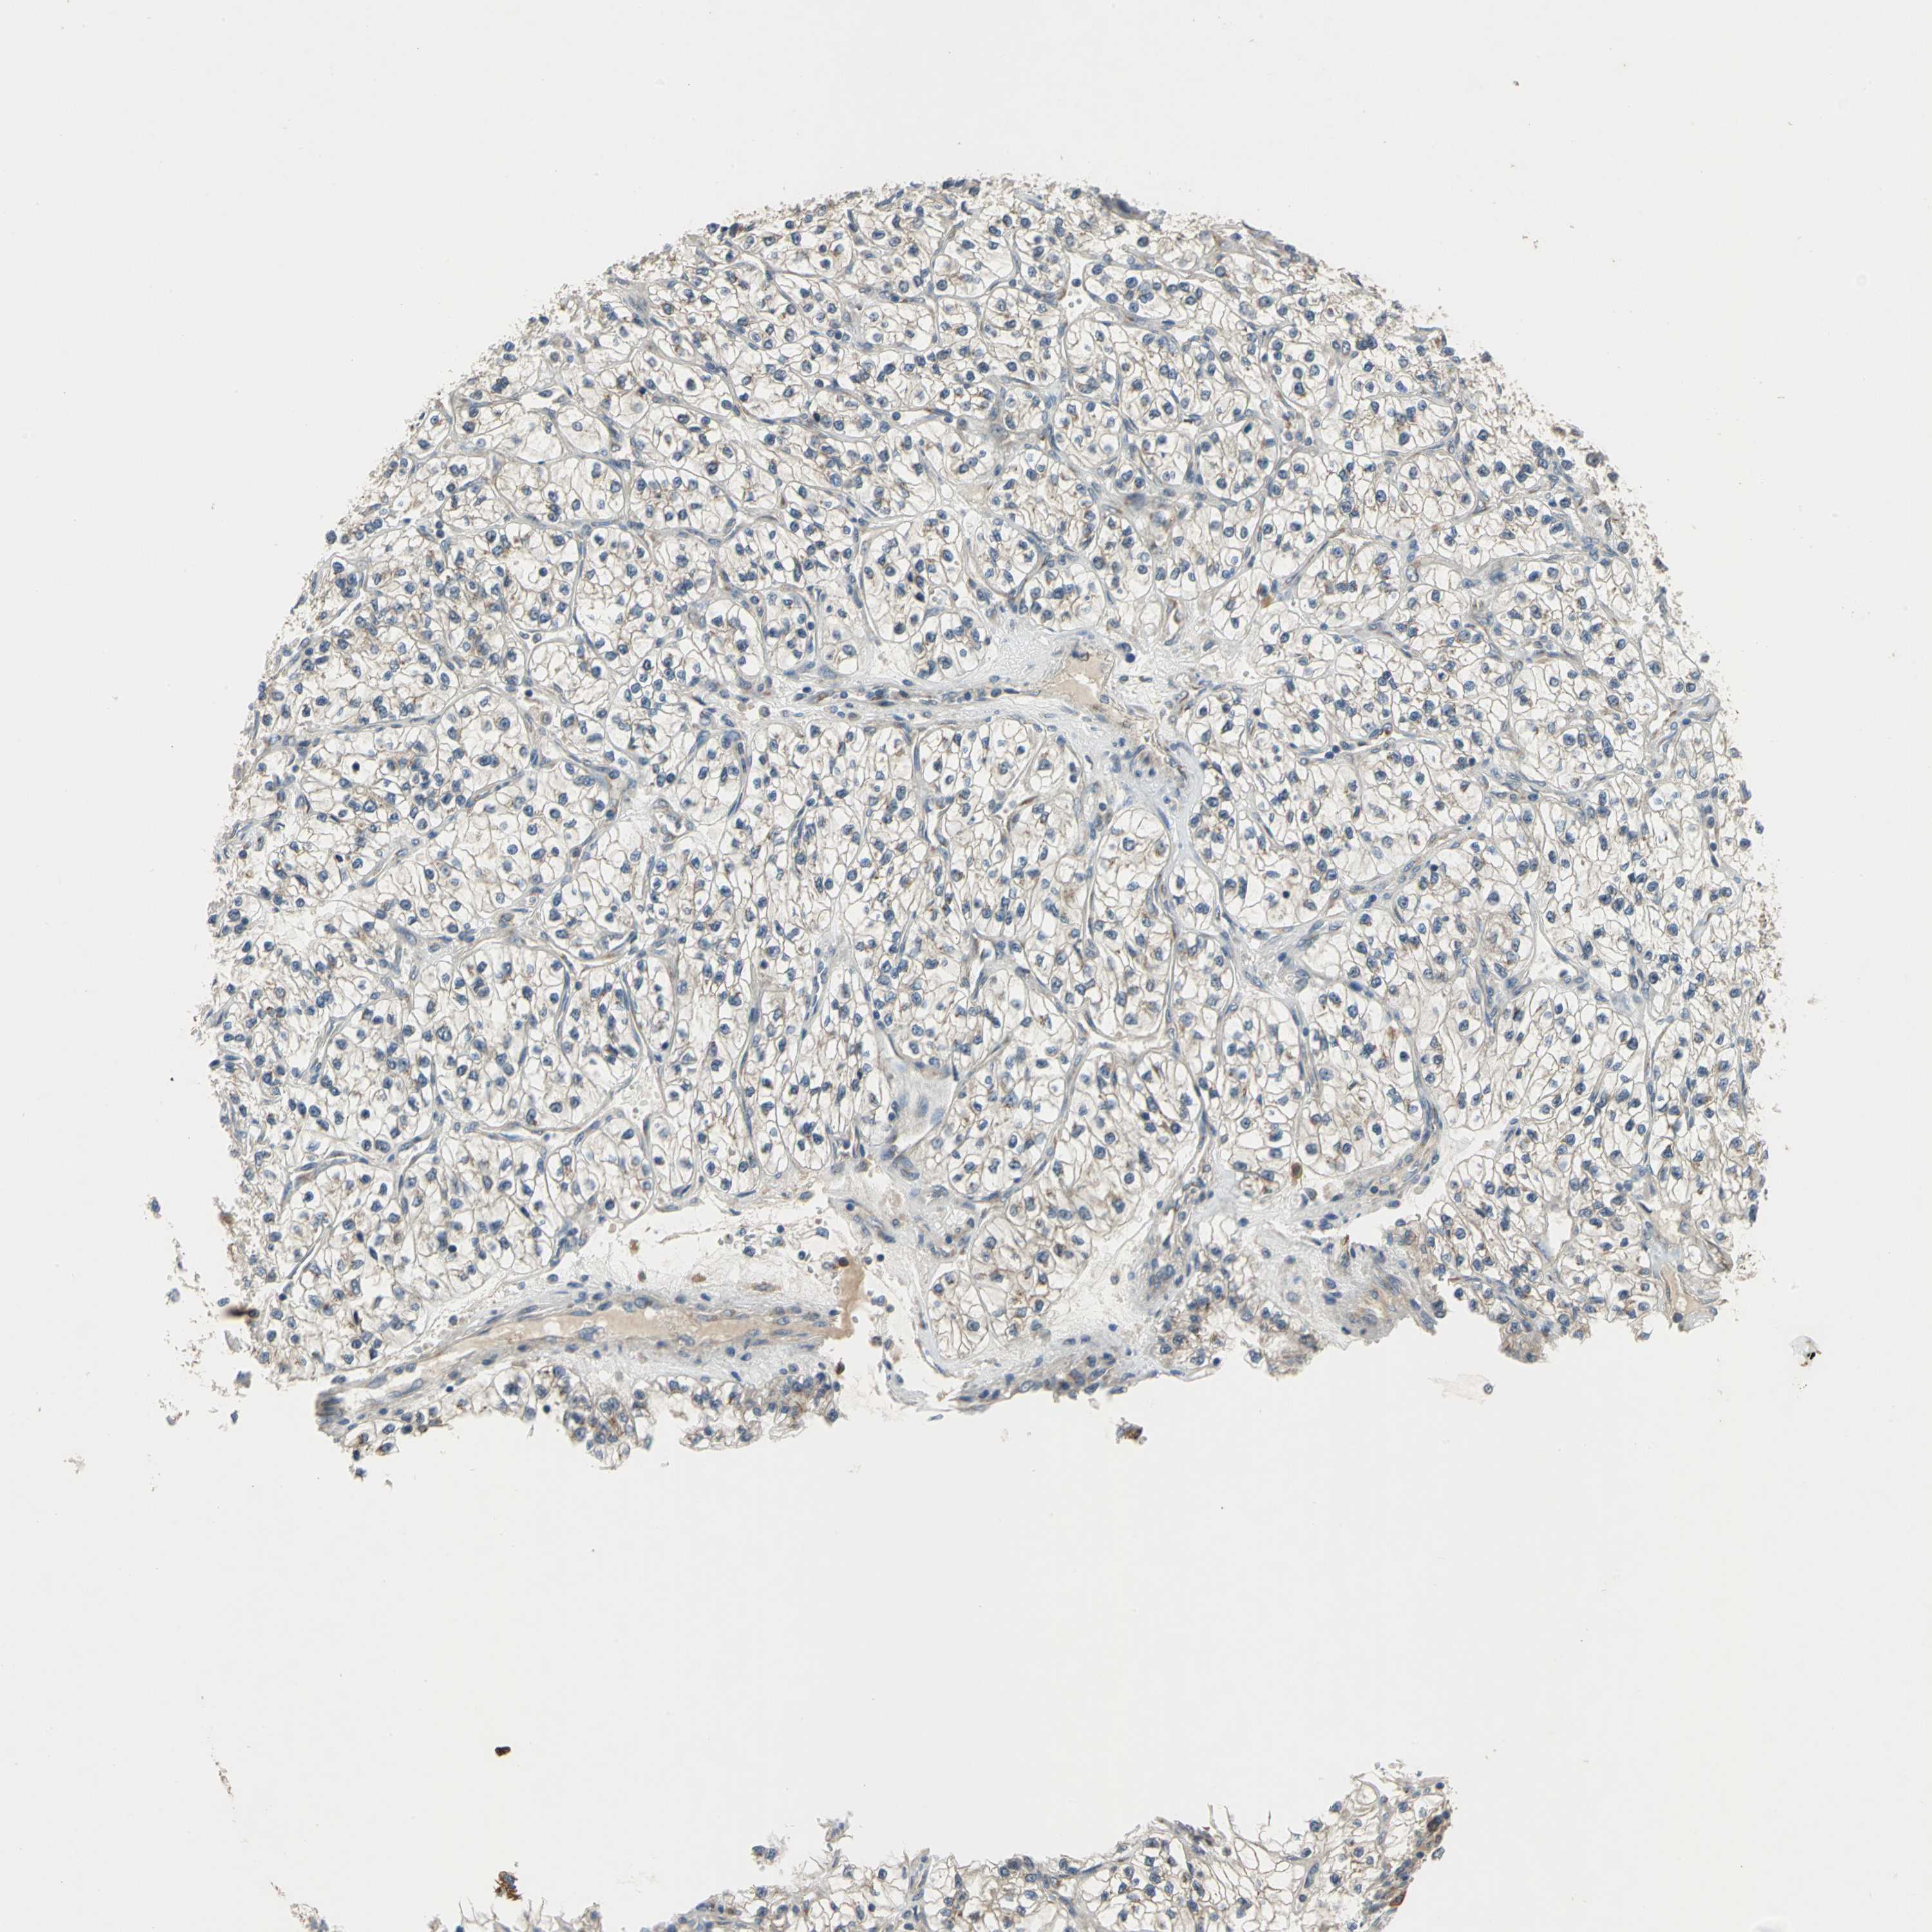

KIDNEY RENAL CLEAR CELL CARCINOMA (VALIDATION) - Interactive survival scatter ploti

The Survival Scatter plot shows the clinical status (i.e. dead or alive) for all individuals in the patient cohort, based on the same data that underlies the corresponding Kaplan-Meier plots. Patients that are alive at last time for follow-up are shown in blue and patients who have died during the study are shown in red.

The x-axis shows the expression levels (FPKM) of the investigated gene in the tumor tissue at the time of diagnosis. The y-axis shows the follow-up time after diagnosis (years). Both axes are complimented with kernel density curves demonstrating the data density over the axes. The top density plot shows the expression levels (FPKM) distribution among dead (red) and alive patients (blue). The right density plot shows the data density of the survived years of dead patients with high and low expression levels respectively, stratified using the cutoff indicated by the vertical dashed line through the Survival Scatter plot. This cutoff is automatically defined based on the FPKM cutoff that minimizes the p-score. The cutoff can be changed by dragging the vertical line or by entering a cutoff value in the square labeled "Current cut-off".

Under the Survival Scatter plot the p-score landscape (black curve; left axis) is shown together with dead median separation (red curve; right axis). Dead median separation is the difference in median mRNA expression between patients who have died with high and low expression, respectively. It is calculated as follows: median FPKM expression of dead patients with high expression - median FPKM expression of dead patients with low expression. This is intended to aid the user in visually exploring custom cutoffs and the associated p-scores and dead median separation.

Individual patient data is displayed and can be filtered by clicking on one or more of the category buttons on the top of the page. Categories describing expression level and patient information include: high, low, alive, dead, female, male and tumor stages. The scale of the x-axis can be toggled between linear and log-scale by clicking on the "x log" button. Mouse-over function shows TCGA ID, patient information and mRNA expression (FPKM) for each patient.

& Survival analysisi

Kaplan-Meier plots summarize results from analysis of correlation between mRNA expression level and patient survival. Patients were divided based on level of expression into one of the two groups "low" (under cut off) or "high" (over cut off). X-axis shows time for survival (years) and y-axis shows the probability of survival, where 1.0 corresponds to 100 percent.

NFKBIE is not prognostic in Kidney Renal Clear Cell Carcinoma (validation)

Best expression cut offi

Based on the FPKM value of each gene, patients were classified into two groups and association between prognosis (survival) and gene expression (FPKM) was examined. The best expression cut-off refers the FPKM value that yields maximal difference with regard to survival between the two groups at the lowest log-rank P-value. Best expression cut-off was selected based on survival analysis .

When clicking on this number, the vertical dashed line indicating cut-off, the interactive survival plot, and the Kaplan-Meier curve will be adjusted to show results based on the best expression cut-off.

: 18.93

P scorei

Log-rank P value for Kaplan-Meier plot showing results from analysis of correlation between mRNA expression level and patient survival.

N/A

TCGA RNA samplesi

RNA-seq data is reported as average FPKM (number Fragments Per Kilobase of exon per Million reads), generated by the The Cancer Genome Atlas (TCGA) .

Normal distribution across the dataset is visualized with box plots, shown as median and 25th and 75th percentiles. Points are displayed as outliers if they are above or below 1.5 times the interquartile range. FPKM values of the individual samples are presented next to the box plot.

Average pTPM 31.4

Number of samples 100